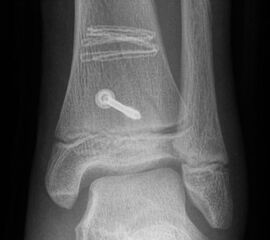

Fugengelenkfrakturen treten typischerweise vor dem 10. Lebensjahr auf, in einer Phase, in welcher die Wachstumsfugen noch weit offen sind. Dieser Frakturtyp betrifft fast ausschließlich den medialen Malleolus. Laterale Frakturen sind extrem selten, teilweise kommt es zu lateralen Bandverletzungen oder Fugenschaftfrakturen der distalen Fibula. Die Frakturlinie verläuft in einer Verlängerungslinie von der medialen Taluskante nach proximal. Häufig stellen sich Verletzungen des Innenknöchels im Röntgenbild schlechter dar, insbesondere wenn die Aufnahmen verdreht sind oder die Ebene der Fraktur bei geringer Dislokation verkippt zur Röntgenebene liegt. Besteht klinisch der geringste Hinweis auf eine Verletzung des Innenknöchels, muss aufgrund der Tragweite der Verletzung durch entsprechende Aufnahmen gegebenenfalls auch Schnittbildverfahren die Verletzung sicher diagnostiziert oder ausgeschlossen werden (Abb. 15).

Behandlungsziel ist die exakte Rekonstruktion der Gelenkfläche sowie die Minimierung des Risikos einer späteren Wachstumsstörung. Dislozierte Frakturen werden offen reponiert, die Osteosynthese erfolgt mit einer Kleinfragmentschraube. Finden sich viele kleine Fragmente kann eine K-Draht Osteosynthese durchgeführt werden. Wird der Innenknöchel operiert, kann bei gleichzeitiger hochgradiger lateraler Instabilität eine Rekonstruktion des lateralen Bandapparats durchgeführt werden. Fibula Frakturen stellen sich meist spontan ein, sodass hier keine zusätzliche Osteosynthese notwendig ist.